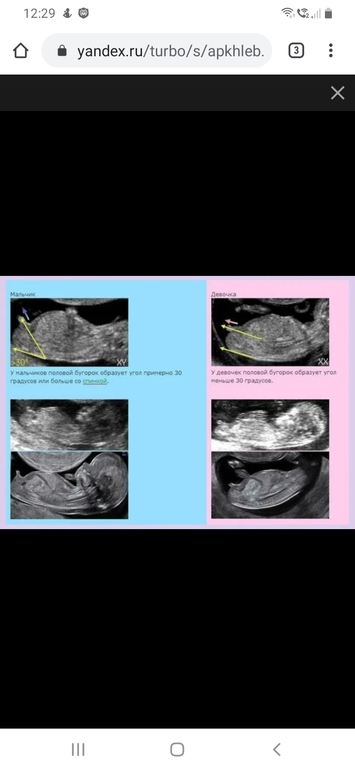

Как я поняла из того, что прочитала - на этом сроке только по положению полового бугорка. У вас на фото он действительно направлен вверх. У меня сейчас я смотрю и тоже теперь понимаю, что параллельно позвоночнику. У вас мальчик, у меня девочка, если все так)

Вот бугорок)